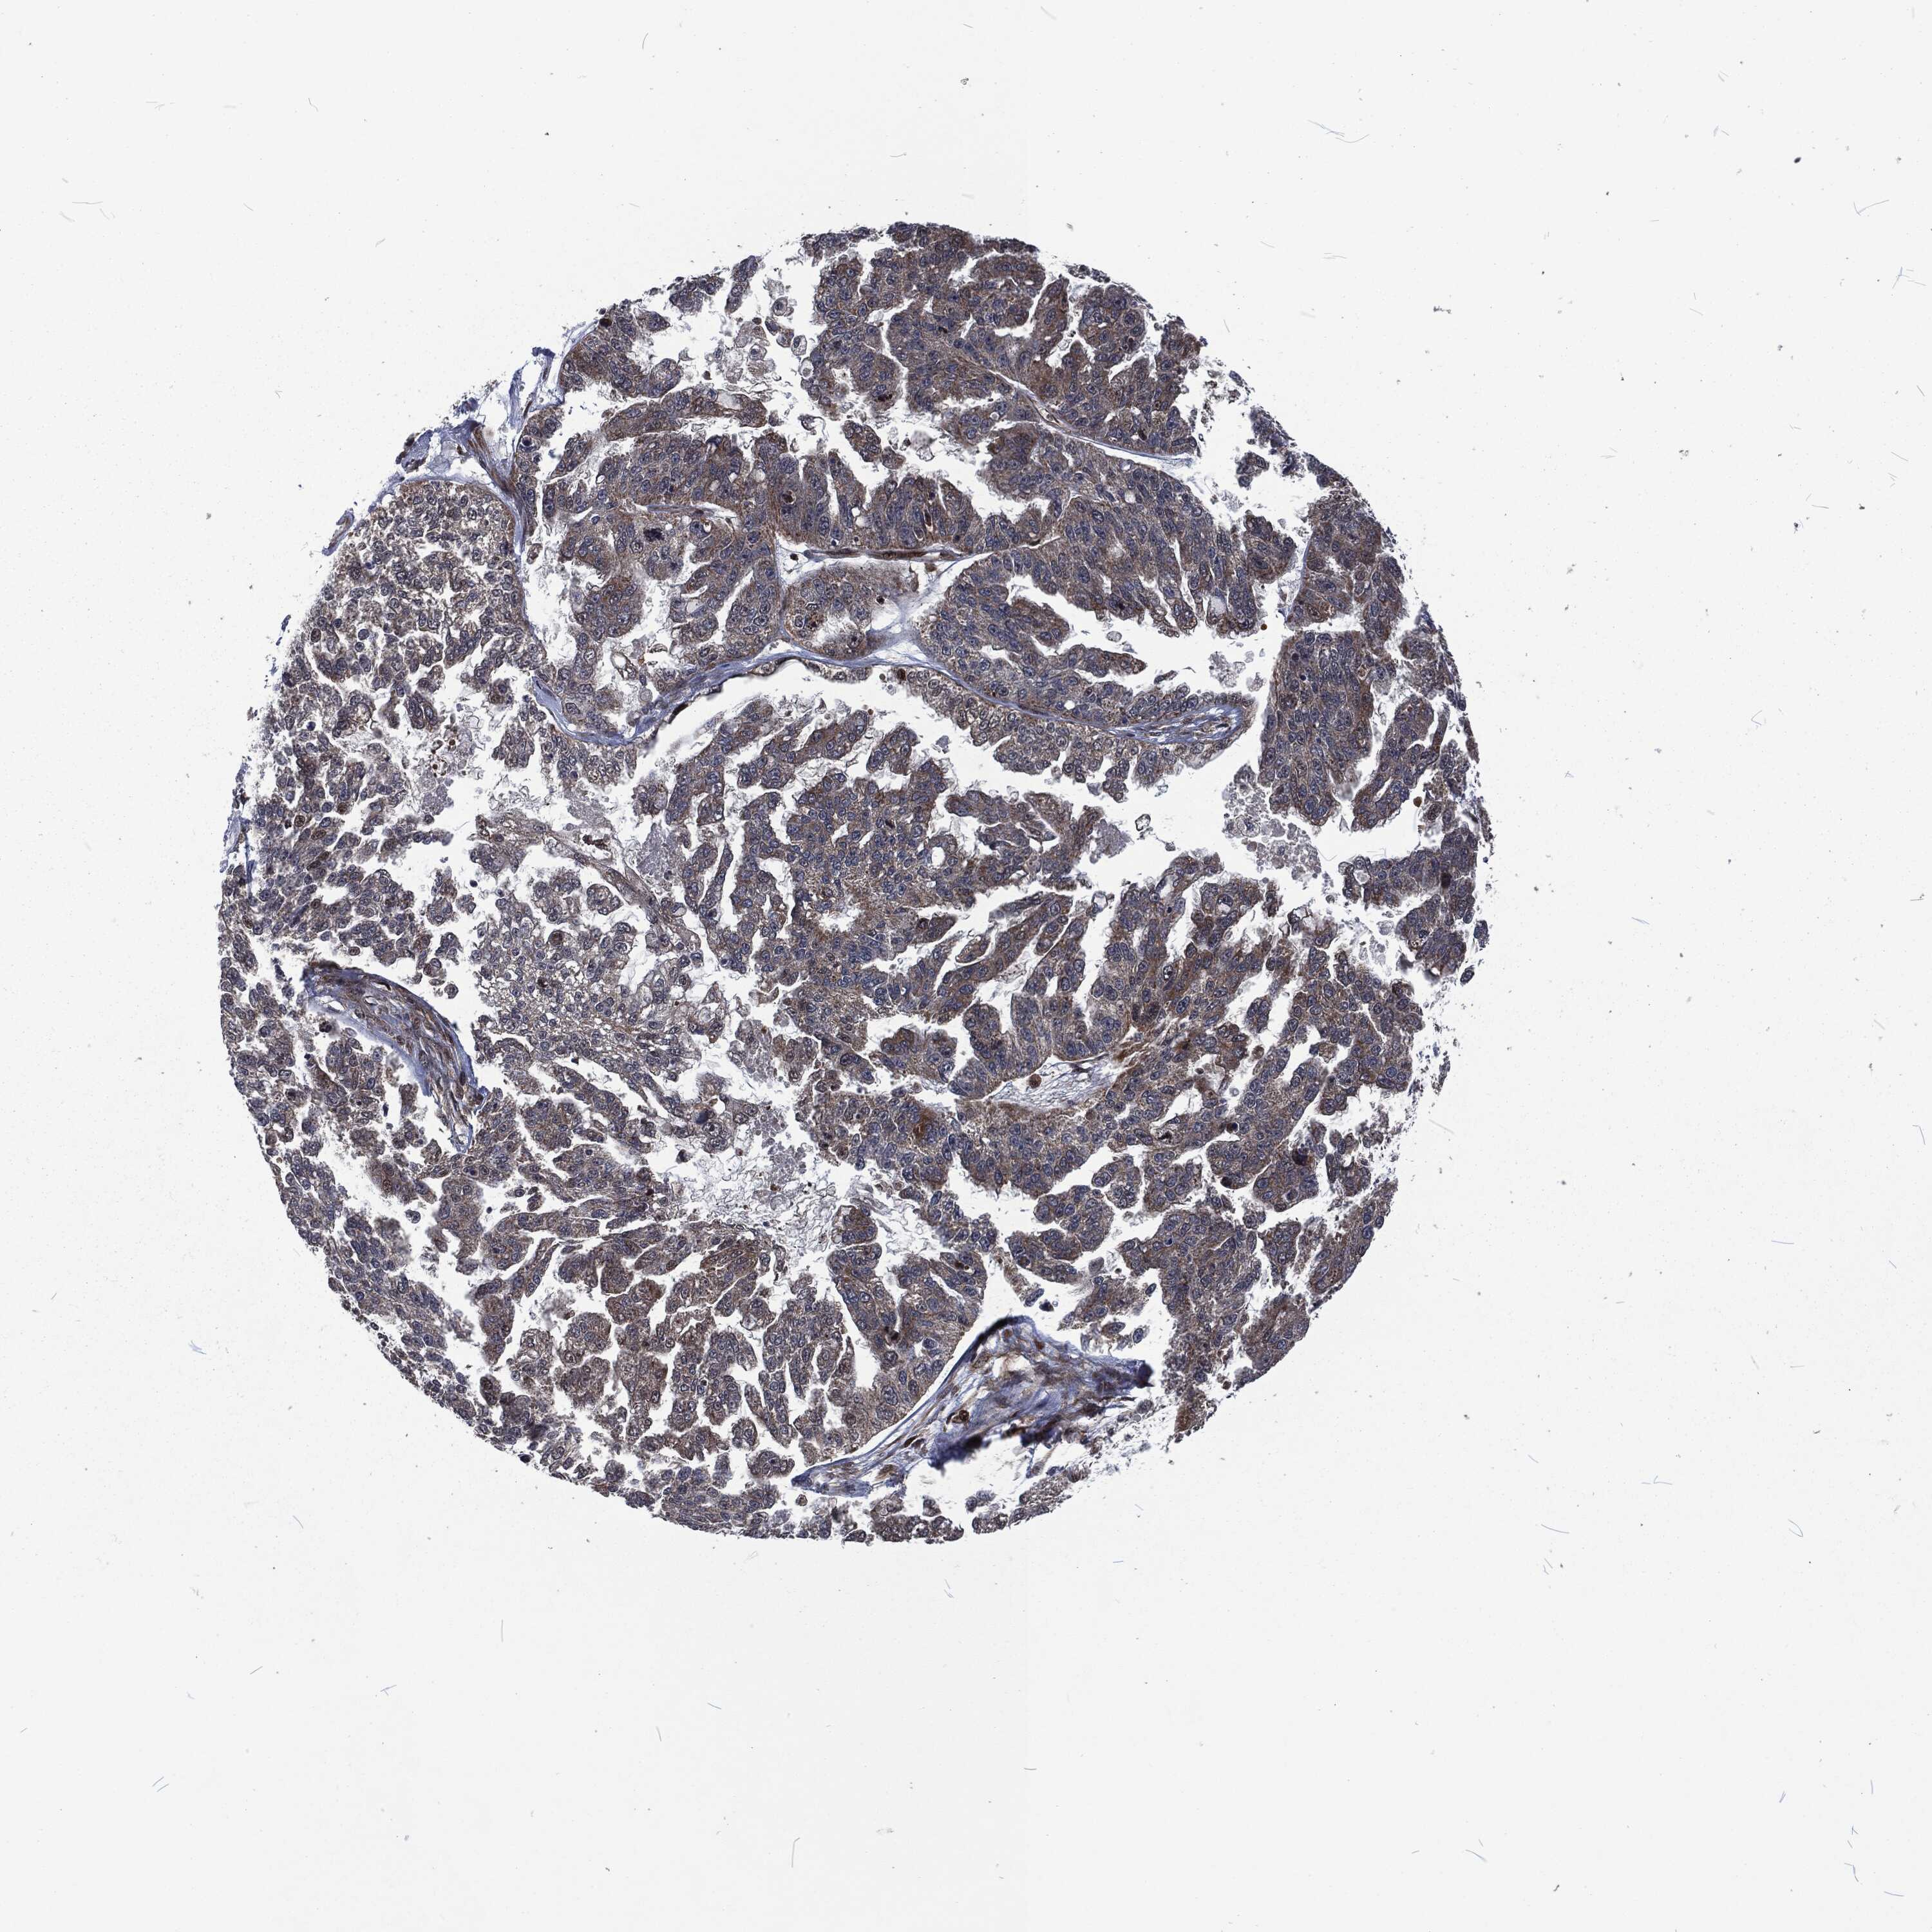

OVARIAN CANCER - Protein expressioni

A mouse-over function shows sample information and annotation data. Click on an image to view it in a full screen mode. Samples can be filtered based on level of antibody staining by selecting one or several of the following categories: high, medium, low and not detected. The assay and annotation is described here.

Note that samples used for immunohistochemistry by the Human Protein Atlas do not correspond to samples in the TCGA dataset.

Antibody stainingi

Antibody staining in the annotated cell types in the current human tissue is reported as not detected, low, medium, or high, based on conventional immunohistochemistry profiling in selected tissues. This score is based on the combination of the staining intensity and fraction of stained cells.

Each image is clickable and will lead to virtual microscopy that enables deeper exploration of all samples and also displays staining intensity scores, fraction scores and subcellular localization as well as patient and tissue information for each sample.

Antibody HPA041430

Antibody HPA062191

Cystadenocarcinoma, serous, NOS

Carcinoma, endometroid

Cystadenocarcinoma, mucinous, NOS

Carcinoma, NOS